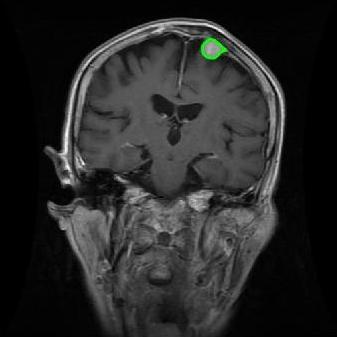

4.2 Comparison with brain tumor MR images segmentation

Brain tumor MRI images represent a critical challenge within the field of medical image analysis, making them a focal point of our research. Various level set models for image segmentation have been applied to brain tumor MRI images, and it is essential to consider the unique characteristics of these images. To validate the excellent performance of the RefLSM, we conduct segmentation comparison experiments on brain MR images and compute the Dice coefficient and Precision values for all evaluated models.

Fig. 4 displays the visual comparison results for segmenting eight brain tumor MR images between the RefLSM and three representative models: the RESLS [8765635], ALF[MA2019201], and L1 model[LIU2019193]. These images exhibit severe intensity inhomogeneity and noise attributable to inconsistent bias field and imaging equipment. The initial level set function (LSF) initialization was consistent across all models, as shown in Fig. 4 (a), which illustrates the initial placement of the zero level contour. For visual clarity, we included the ground truth in Fig. 4 (f). The segmentation outcomes from the RESLS, ALF, and L1 methods are presented in Fig. 4 (b), (c), and (d), respectively.

It is evident from the first and last columns of Fig. 4 (b) that the ALF model tends to become trapped in local minima under severe intensity inhomogeneity. Furthermore, segmentation results presented in the columns 1-4 of Fig. 4 (b) and (c) reveal that both the ALF and L1 models mistakenly segment small isolated or irrelevant regions due to the effects of irregular intensity patterns. Additionally, when weak boundaries are present, as seen in the 1st and 3rd columns of Fig. 4, the RESLS, ALF, and L1 methods fail to accurately identify object boundaries. Consequently, the zero level contours of these models deviate significantly from the objects throughout the level set evolution, causing drastic misalignment after further iterations.

In stark contrast, our proposed method exhibits greater robustness against images exhibiting severe intensity inhomogeneity and weak boundaries. The proposed prior constraint term effectively corrects for intensity inhomogeneity, while the proposed binary level set adeptly reduces noise during the segmentation process.

Overall, these findings demonstrate that the segmentation outcomes produced by our model are more accurate. Besides visual assessment, we calculate the Dice and Precision values of evaluated models for brain tumor segmentation in table 1. Based on these results, we draw a boxplot with scatterplot overlay, as shown in Fig. 6, which displays the data distribution and facilitates comparison of different models’ performance across various brain tumor MR images. We analyze the maximum, median, and minimum, which correspond to the best, median segmentation results, and worst segmentation results, respectively. It is clear that the RefLSM achieves more accurate segmentation results compared to the other models. Moreover, the smaller range of the RefLSM in the boxplot indicates robustness and stability to different images of the brain tumor.